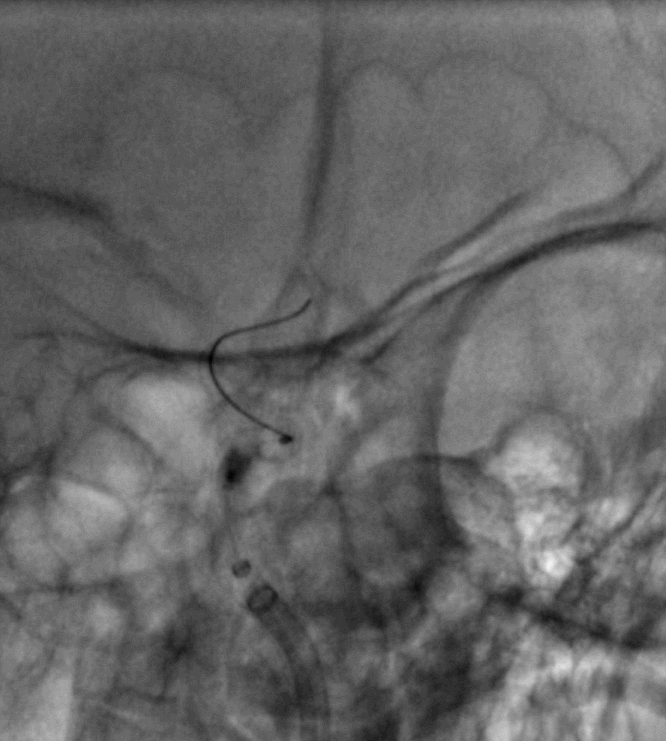

手术过程

Cat5完全释放支架后,拉推送杆后支架近端打开,后将Cat5跟进血流导向装置内尝试“按摩”,支架整体贴壁不够理想。

Cat5通过后海绵窦段狭窄即较前改善

Cat5提供稳定通路,引入3.5mm×10mmHiryu球囊扩张由远端及近端扩张狭窄段及支架贴壁欠佳处

造影示狭窄及贴壁较前进一步改善

导丝成袢,继续“按摩”改善贴壁

“按摩”后再次造影,C2段狭窄仍较明显且贴壁欠佳

再次引入球囊扩张近端

扩张后再次复查造影示支架打开及贴壁较前明显改善

标准正侧位造影未见远端血管栓塞

稀释造影提示支架贴壁可,狭窄改善